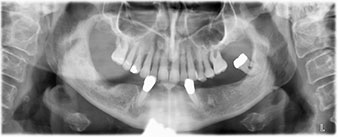

A three-dimensional cone beam computed tomography scan (CBCT, Planmeca) was performed to aid planning and minimize risks. This revealed that the quality and quantity of the available bone were sufficient for the surgery and immediate restoration using the Fast & Fixed method. Following the protocol for this concept, the implants are inserted at 35, 32, 42 and 45. Angling the distal implants by up to 45° shifts the emergence profile to posterior and generates a larger support polygon (Fig. 3).